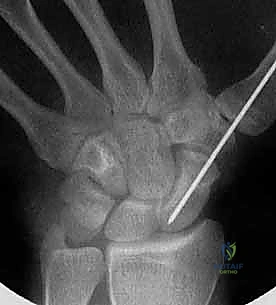

تقنية "التثبيت عن طريق الجلد" (Percutaneous Fixation) هي إجراء جراحي طفيف التوغل (Minimally Invasive). بدلاً من فتح الرسغ، يقوم الجراح بإجراء ثقب صغير جداً في الجلد (لا يتجاوز 3-5 مليمترات). من خلال هذا الثقب، وباستخدام جهاز الأشعة السينية المباشر في غرفة العمليات (C-arm Fluoroscopy)، يتم إدخال سلك توجيهي دقيق، ثم يتم إدخال مسمار خاص يسمى "مسمار ضغط بدون رأس" (Headless Compression Screw) مثل مسمار هيربرت (Herbert Screw).

الخطوة 2: تحديد مسار المسمار بدقة (Guidewire Placement)

هذه هي الخطوة الأكثر أهمية والتي تتطلب مهارة استثنائية. يقوم د. هطيف بعمل شق صغير جداً (بضعة مليمترات). باستخدام جهاز الأشعة، يقوم بإدخال سلك معدني